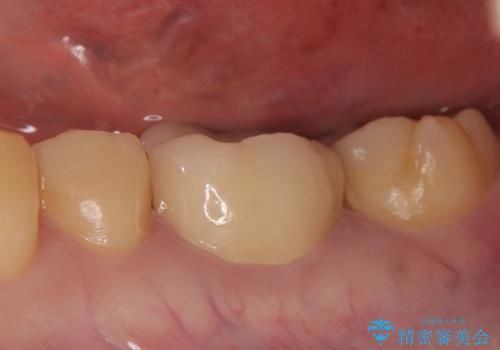

オールセラミッククラウン 歯根破折→抜歯→ブリッジ